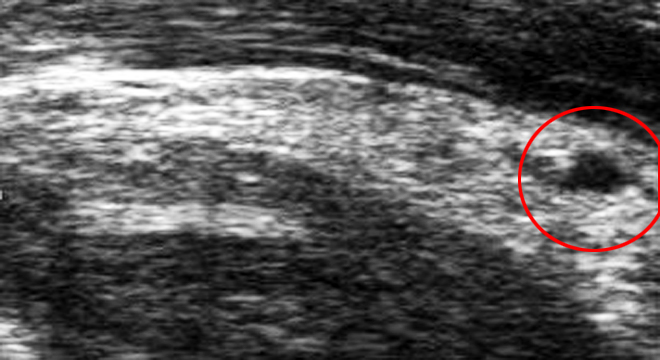

Muskelzerrung: im Ultraschallbild Riss und Bluterguss

Zur Diagnose einer Muskelzerrung werden verschiedenen Untersuchungen und Abklärungen durchgeführt. Dazu gehören unter anderem:

• Erhebung der Krankengeschichte: Die Beschreibung der Schmerzen und der Funktion des betroffenen Gliedes lässt bereits auf das Ausmass der Verletzung schliessen

• Klinische Untersuchung des betroffenen Körperteils

• Ultraschall: Lokalisation und Ausmass eines Risses und eines Blutergusses (Hämatom) können genau bestimmt werden.